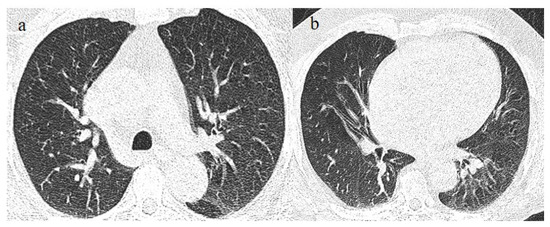

| Typical Appearance | GGOs with a crazy-paving pattern and consolidations in a peripheral and posterior or central-peripheral distribution; multilobar involvement; vascular enlargement, the halo and reversed halo sign; subpleural and parenchymal bands; and architectural distortion. They were predominant since the Delta wave. |

| Indeterminate Appearance | GGOs and consolidations with a unilateral, central, or upper-lobe distribution. |

| Atypical Appearance | Lobar consolidation, lung nodules or masses, miliary patterns, tree-in-bud patterns, cavitation, pleural effusion, central distribution, and lymphadenopathy. Atypical appearances were predominant during the Omicron waves. |

| Typical appearance | From the wild-type to the Delta variant. | Askani et al., 2022 [67] | The Delta variant presented more frequent typical features with more extensive lung involvement than the Omicron variant. The Omicron variant was more frequently associated with the absence of pneumonia. |

| Inui et al., 2021 [68] | Typical findings were characteristic of the wild type to the Delta variant. GGOs with consolidation and repair changes were more frequent in the Delta variant. The Delta variant also showed more rapid pneumonia progression than the wild-type and Alpha variants. | ||

| Ito et al., 2022 [54] | Peripheral GGO distributions were more frequent in the Alpha and Delta variants than the Omicron variant. | ||

| Kirka et al., 2022 [27] | Typical features were found in 40.8% of patients with the wild-type variant and 1.7% of patients with the Omicron variant. | ||

| Lee et al., 2023 [28] | Typical CT patterns were more frequent in the Delta group (76%) than in those with the Omicron variant (42%). | ||

| Yang et al., 2022 [78] | Of patients with the Alpha variant, 86.84% presented typical COVID-19 pneumonia CT features. | ||

| Yoon et al., 2023 [69] | Only 32% of patients with the Omicron variant presented typical findings, compared with 57% of the Delta variant cases. | ||

| Indeterminate appearance | Omicron variant | Ito et al., 2022 [54] | Cluster-like GGOs in the Omicron wave. |

| Atypical appearance | Omicron Variant | Hang et al., 2023 [75] | Patients infected with the Omicron variant presented a significantly higher prevalence of nodules, tree-in-bud patterns, and halo signs than patients with the original strain. |

| Ito et al., 2022 [54] | Prevalence of non-peripheral distribution with random distribution during the Omicron wave. | ||

| Lee et al., 2023 [28] | Peribroncovascular pneumonia with the Omicron variant and lower rates of severe pneumonia than the Delta variant. | ||

| Tsakok et al., 2023 [77] | Patients with an Omicron infection presented a greater frequency of bronchial wall thickening but less severe disease compared with the Delta variant. | ||

| Yang et al., 2022 [78] | Only 1.3% of patients infected with the Omicron variant had foci of pneumonia, and the GGOs were unilateral and centrilobular. | ||

| Yoon et al., 2023 [69] | Peribroncovascular GGOs or centrolobular foci during the Omicron wave with less extensive pneumonia. |